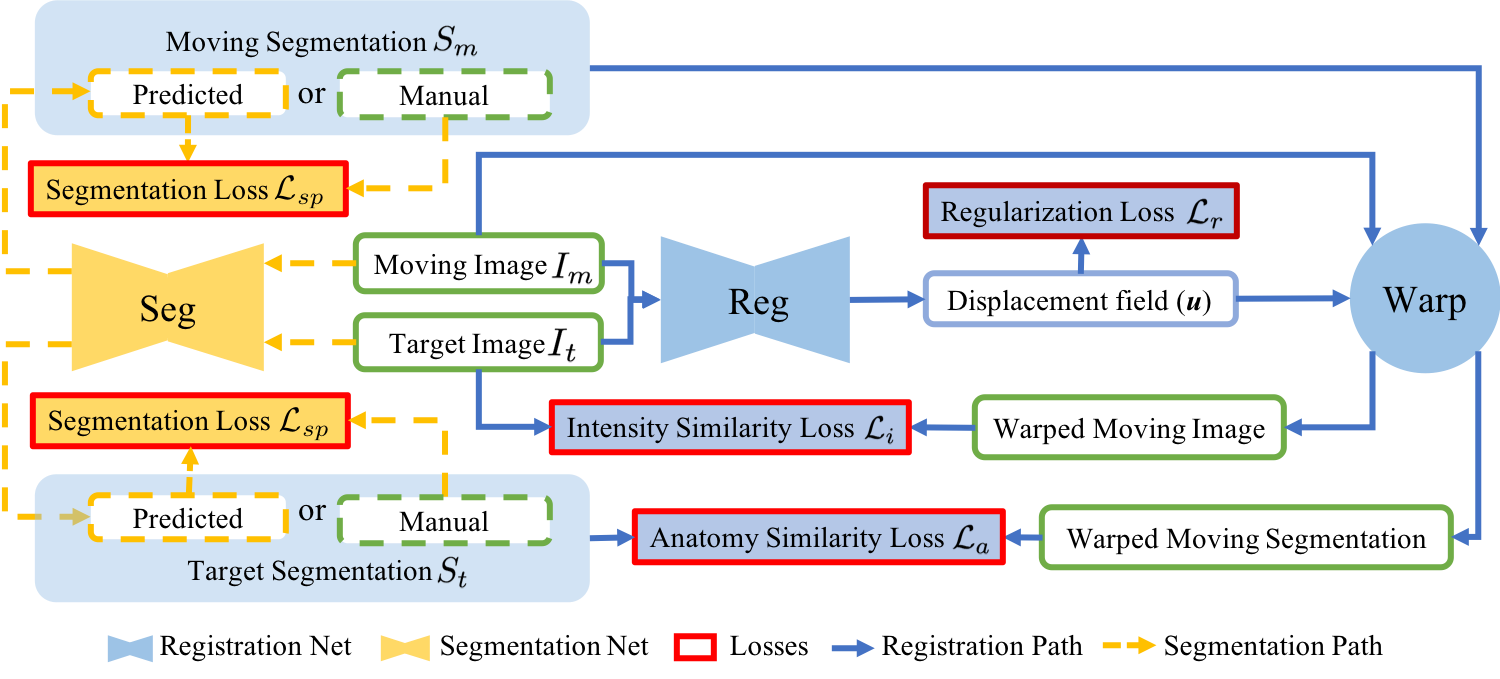

2 Method

Our goal is to improve registration and segmentation accuracy when few manual segmentations are available for a large set of images by jointly learning a segmentation and a registration network. Fig. 1 illustrates our approach consisting of two parts: weakly-supervised registration learning (solid blue lines) and semi-supervised segmentation learning (dashed yellow lines). Our loss is the weighted sum of the registration regularization loss (), the image similarity loss (), the anatomy loss () penalizing segmentation dissimilarity, and the supervised segmentation loss (). The losses {, , } drive the weakly supervised learning of registration (Sec. 2.1) and the losses {, } drive the semi-supervised learning of segmentation (Sec. 2.2). Sec. 2.3 details the implementation.

2.1 Weakly-supervised Registration Learning

Given a pair of moving and target images and , a registration network with parameters predicts a displacement field . This then allows warping the moving image to the target image space, , where is the deformation map and is the identity transform. A good map, , maps related anatomical positions to each other.

Unsupervised registration learning optimizes over an intensity similarity loss (penalizing appearance differences between and ) and a regularization loss on to encourage smooth transformations. Adding weak supervision by also matching segmentations between the target image () and the warped moving image () via an anatomy similarity loss can improve registrations [3]. Weakly-supervised registration learning is then formulated as:

| (1) |

with weights . In practice, while a large set of images are often available, few of them have manual segmentations. In contrast to existing work, we estimate missing moving or target segmentations via our segmentation network (see Fig. 1). Hence, we provide weak supervision for every training image pair.

2.2 Semi-supervised Segmentation Learning

The segmentation network with parameters takes an image as input and generates probabilistic segmentation maps for all semantic classes: . In addition to the typical supervised segmentation loss where is a given manual segmentation, the anatomy similarity loss for registration also drives segmentation learning when or are predicted via for unlabeled images. Specifically, we define these losses as:

with weights . teaches to segment an unlabeled image such that the predicted segmentation matches the manual segmentation of a labeled image via . In the case where the target image is unlabeled, is equivalent to a supervised segmentation loss on , in which the single-atlas segmentation is the noisy true label. Note that we do not use two unlabeled images for training and does not train the segmentation network when both images are labeled. We then train our segmentation network in a semi-supervised manner as follows:

| (2) |